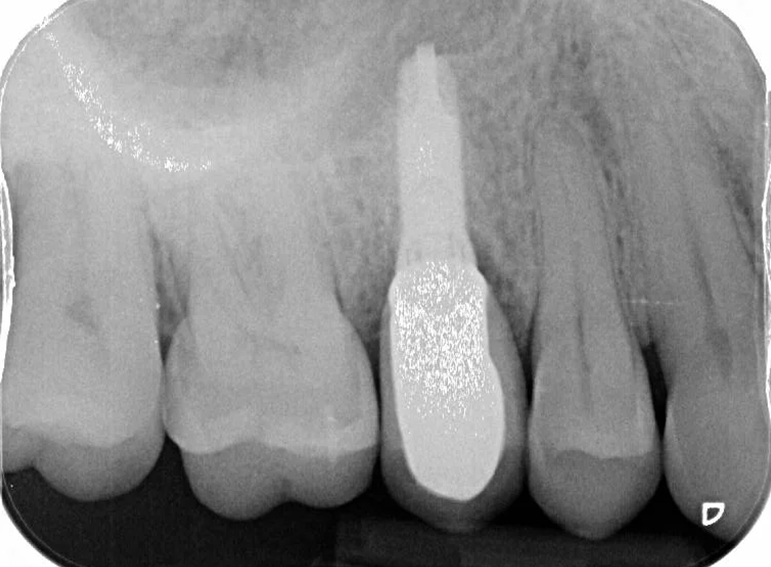

Removal of infected premolar and replacement with a temporary adhesive bridge and implant.